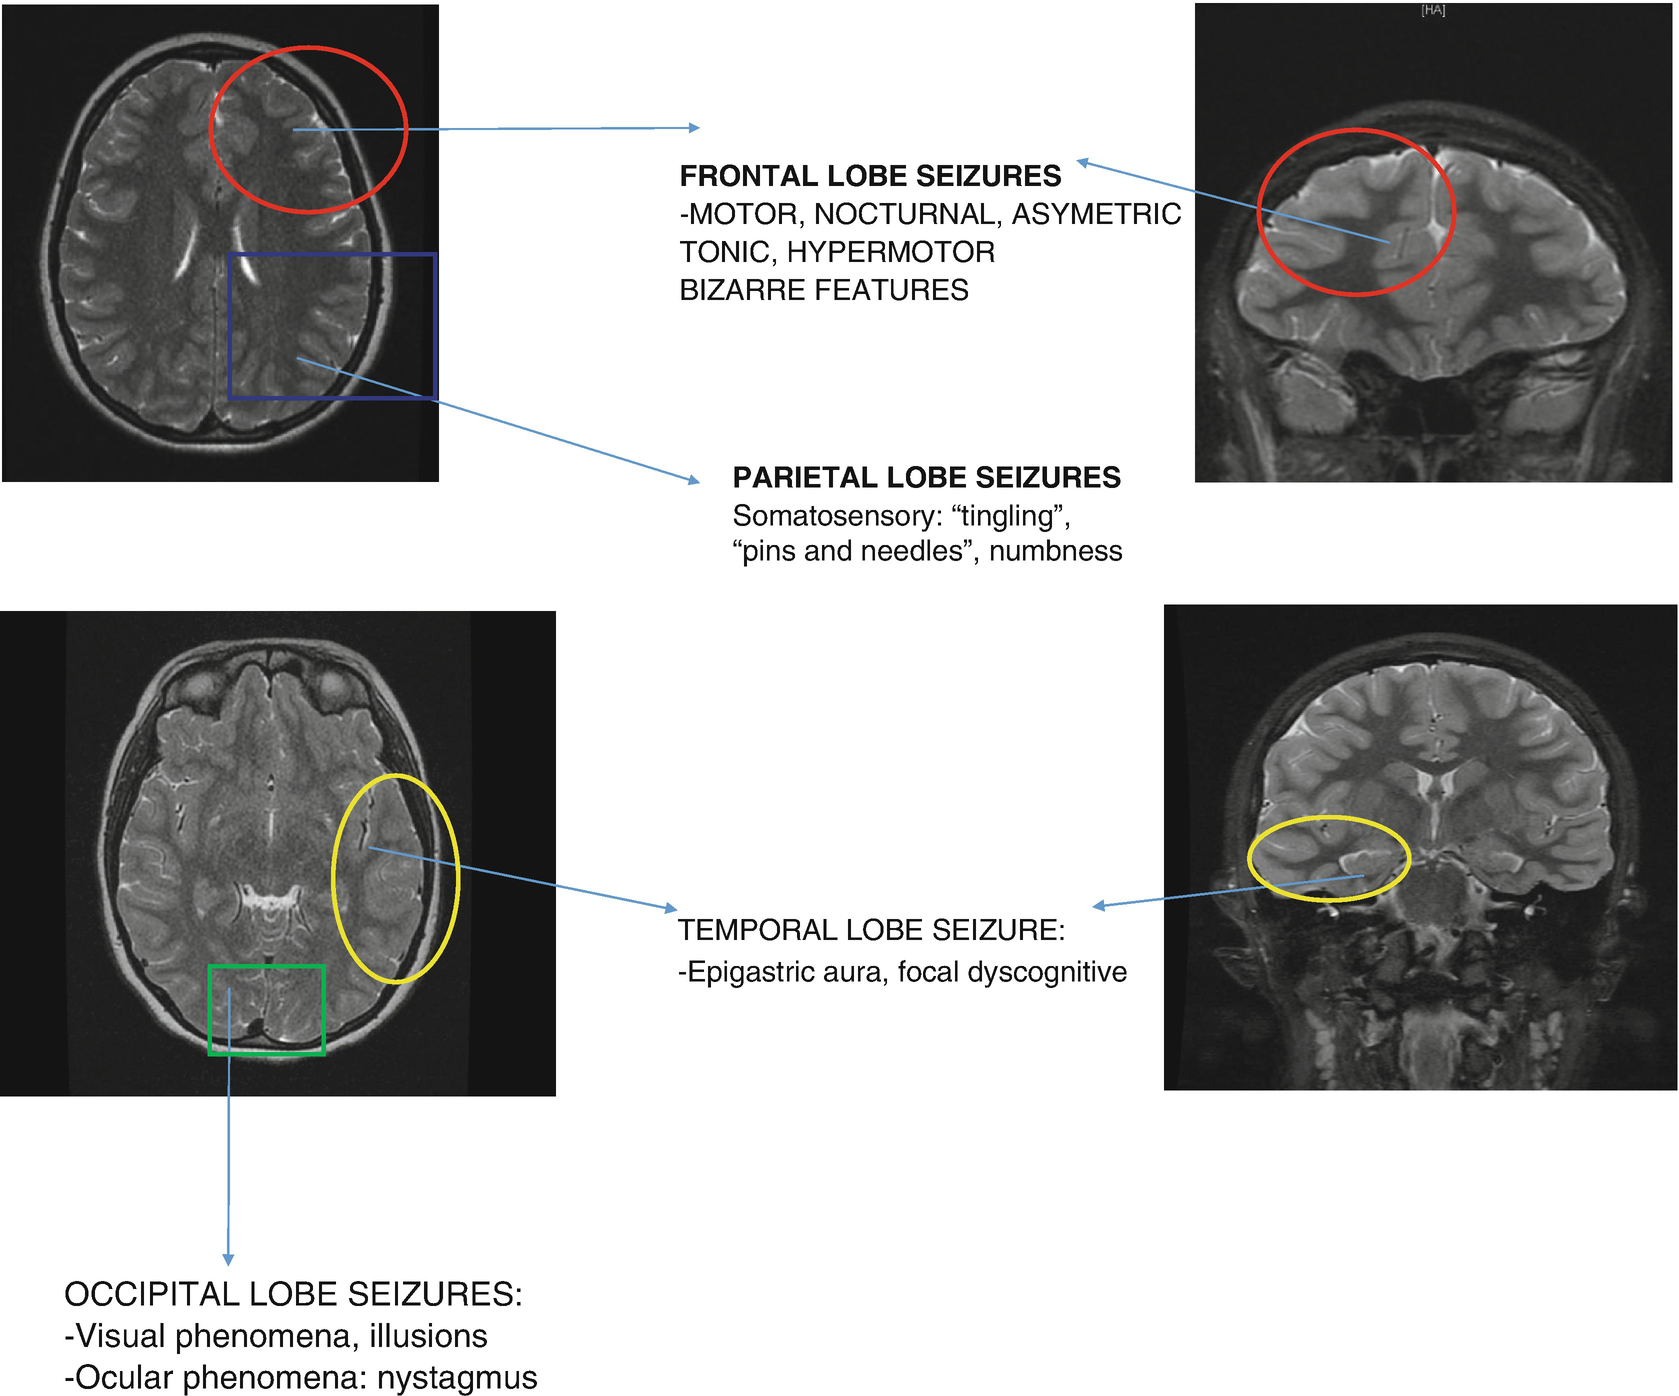

Figure 535 From Focal Epileptogenic Lesions Semantic Scholar

Amazoncom Pediatric Neurology Part I Chapter 53 Focal

Focal Epileptogenic Lesions Sciencedirect